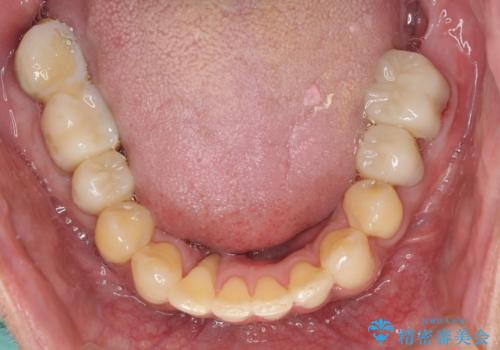

歯列不正と歯周病 総合歯科治療による全顎治療

- 前歯がのデコボコや、奥歯に咬んだときに痛みがあるとのことで来院された患者様です。

全体的に問題が多く、全てをしっかりと治療したいとのことでした。

全体的に中等度の歯周病と診断されたため、歯周外科処置やインプラントによる咬合回復から進めて行き、矯正治療による歯列改善を行った後にオールセラミッククラウンにて補綴することとしました。

歯槽骨の再生治療を行ったため、外科処置後の静置期間がながくなり、4年弱の治療期間となりました。

初診来院時には矯正治療を行うことは想像していなかったようで、治療後には咬みやすさだけでなく、前歯が大変審美的に仕上がり、患者様には大変満足していただきました。